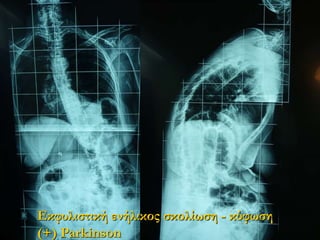

Εκφυλιστική ενήλικος σκολίωση

- κύφωση (+) Parkinson

38.